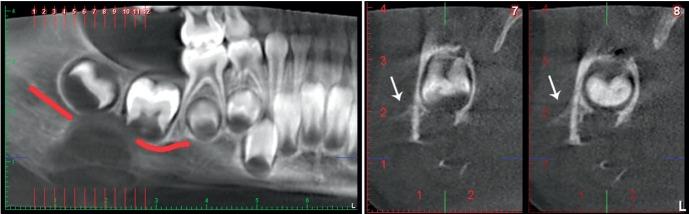

Central odontogenic fibroma (COF) is a rare benign tumor that accounts for 0.1% of all odontogenic tumors. A case of COF (simple type) of the mandible in a four-year-old boy is described in this report. The patient showed asymptomatic swelling in the right inferior border of the lower jaw for one week. A panoramic radiograph showed a poorly-defined destructive unilocular radiolucent area. Cone-beam computed tomography showed expansion and perforation of the adjacent cortical bone plates. A periosteal reaction with the Codman triangle pattern was clearly visible in the buccal cortex. Since the tumor had destroyed a considerable amount of bone, surgical resection was performed. No recurrence was noted.

中央性牙源性纤维瘤(COF)是一种罕见的良性肿瘤,占所有牙源性肿瘤的0.1%。本报告描述了一名4岁男孩下颌骨COF(单纯型)病例。患者下颌右下缘出现无症状肿胀一周。全景X线片显示一个边界不清的单房性透射性破坏区。锥形束计算机断层扫描显示相邻皮质骨板膨胀和穿孔。颊侧皮质可见明显的骨膜反应,呈科德曼三角模式。由于肿瘤已破坏了大量骨质,故行手术切除。未观察到复发情况。